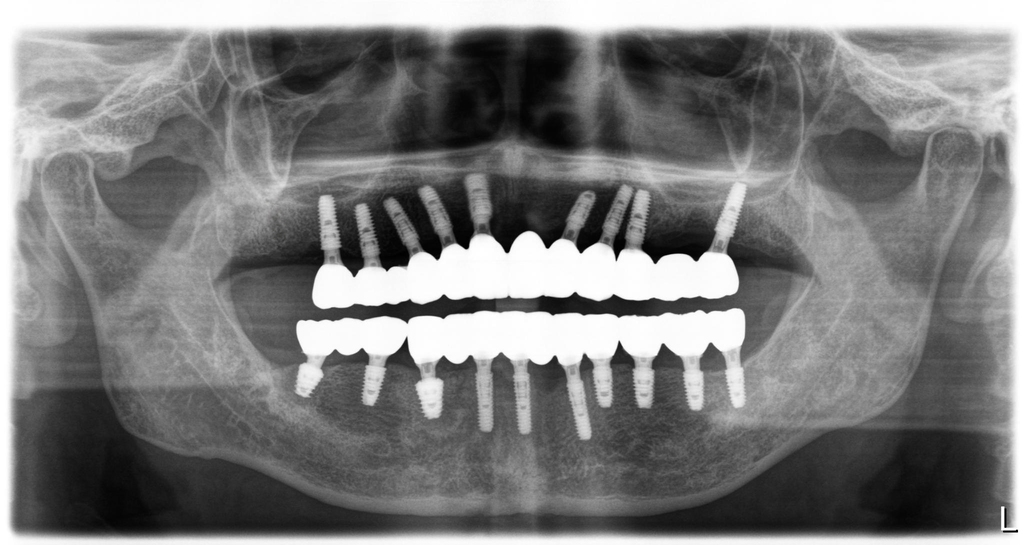

치료는 환자분의 우측 아래 어금니를 발치하는 것으로 시작되었습니다. 이 부위는 뼈 상태가 양호하여 발치와 동시에 임플란트를 심을 수 있었습니다. 이후, 뼈 상태가 좋지 않아 즉시 식립이 어려웠던 윗니 부위는 약 6개월간 뼈가 회복될 때까지 기다렸다가 시술을 진행했습니다. 이처럼 필요한 부위를 순차적으로 치료하고 기다리는 과정을 반복하여, 3년이라는 기간에 걸쳐 모든 치료를 성공적으로 마무리했습니다. 최종 보철물은 여러 개의 임플란트를 연결하는 나사 구조를 적용하여 안정성을 극대화했고, 맞춤형 티타늄 지대주를 이용한 지르코니아 보철로 기능과 심미성 모두를 완벽하게 재건했습니다.